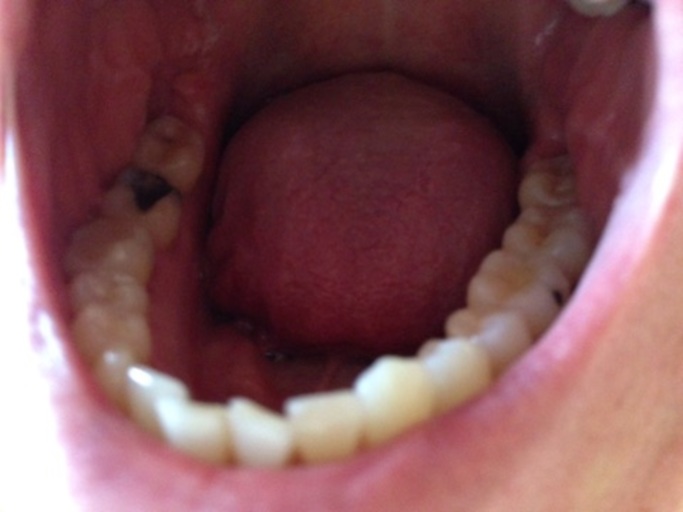

Why did my daughter's tooth turn grey after her dentist appointment?

Hey I have a daughter (5) who has had a cavity on the front of her front tooth since she was 2. It\'s just a tiny little hole. We went to the dentist when she was 2 but they wanted to put a silver cap on it so I never got it done. I\'ve taken good care of it to make sure it didn\'t get worse and it hasn\'t. She went to the dentist last week and when she came out she had this sticky stuff all over her teeth(yellowish in color) the next morning her tooth was completely grey! It was perfectly white before her apt! They also said they needed to Cap it. Did they do something to make it decay more for the procedure they want to do?? I don\'t know what was on her teeth but it wasn\'t the stuff to prevent further cavities because they said they\'d do that at the next apt.